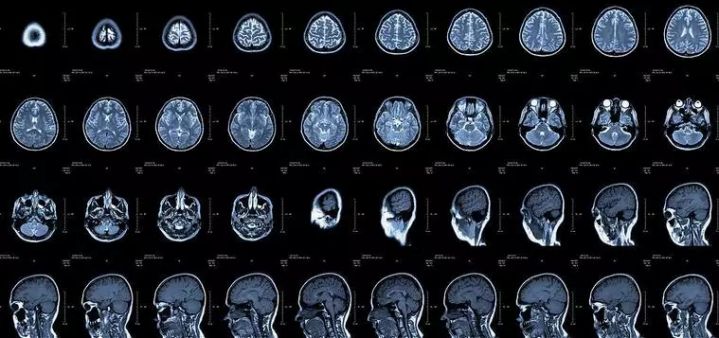

核磁共振:摇一摇再看

核磁共振机使用较强大的磁场,使人体中所有水分子磁场的磁力线方向一致,这时磁共振机的磁场突然消失,身体中水分子的磁力线方向,突然恢复到原来随意排列的状态。简单说就相当于用手摇一摇,让水分子振动起来,再平静下来,感受一下里面的振动。所以,核磁共振(MRI)也被戏说为是摇摇看的检查。